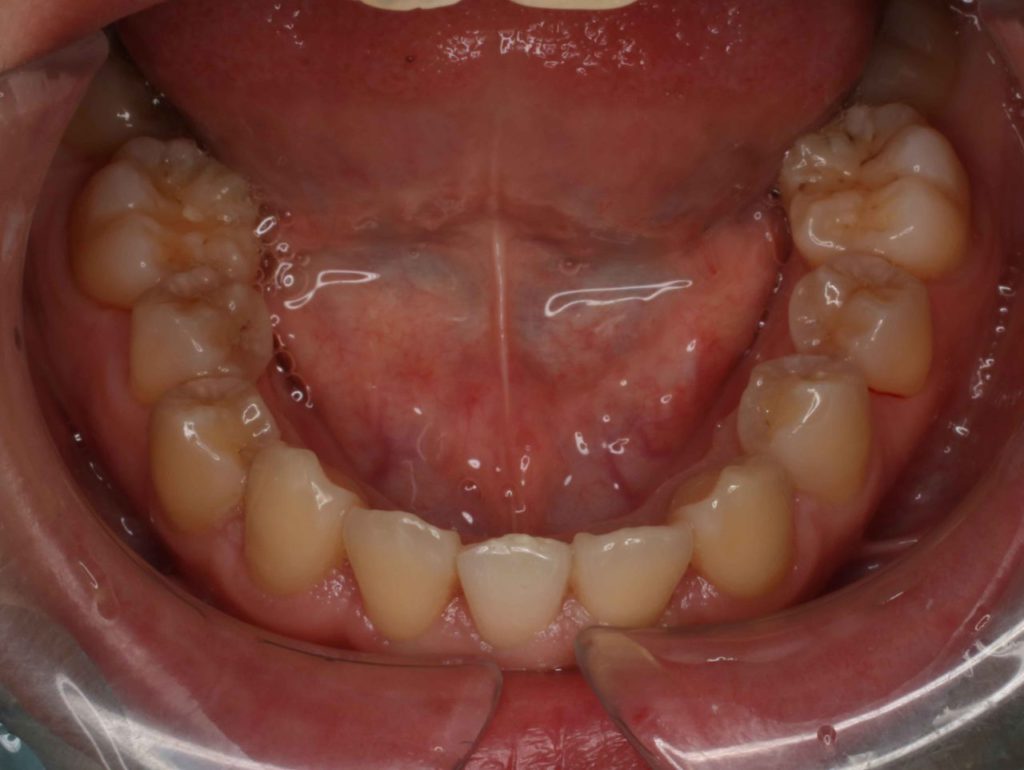

Before

上下顎前歯部で矯正治療はできないかと相談されました、検査の結果上顎は翼状捻転のため配列するためのスペースをつくるために

IPR(隣接面のスライスカット) を行う、下顎の叢生は大きいので前歯抜歯を行う治療計画を提案しました

下顎抜歯時に出来るだけ前歯の歯がない期間を少なくしたいと希望されました。

年齢 29歳

性別 女性

症状 透明で目立たない装置

治療内容 上下前歯叢生

治療期間 1.5年